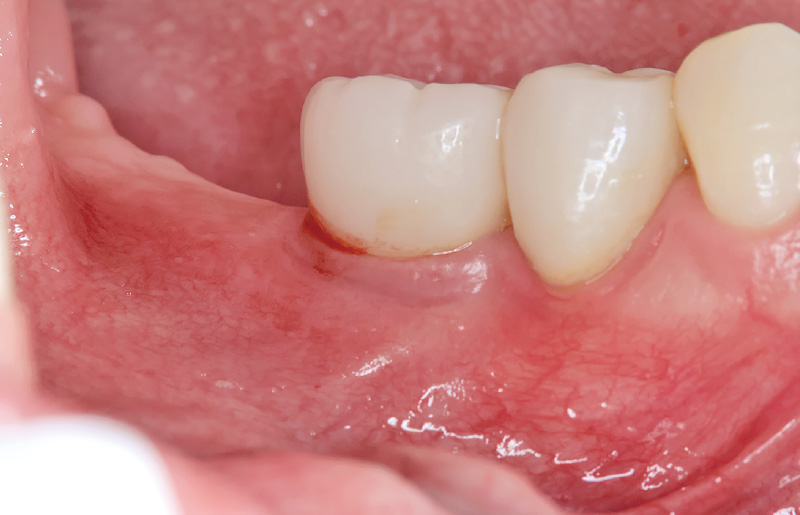

図8 再GBR後4か月。「アドベール SH」にてアクセルホールをパンチアウトして、上部構造をスクリューリテインにて固定する。再発防止のため、骨の成熟を待って遊離歯肉移植が必要と思われる。 -